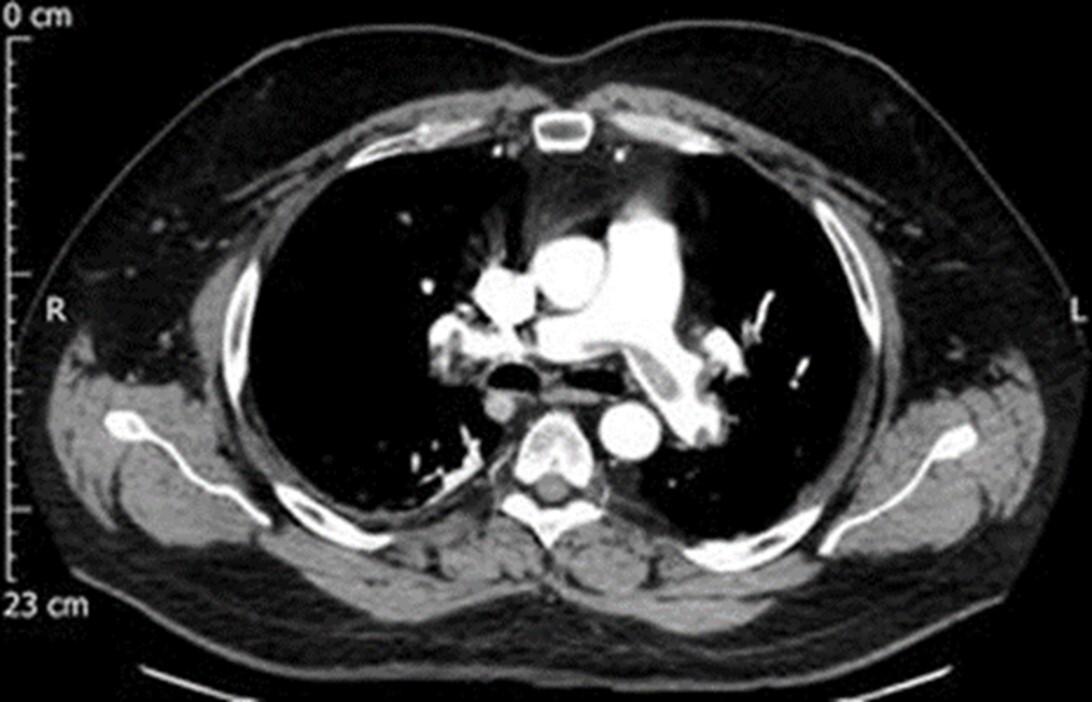

Q

You end up with the following CTPE scan. An ROI placed in the pulmonary trunk yields a mean HU of 100. Is the scan optimal, yes or no, and why?

A

No, it is not optimal, the pulmonary trunk is not opacified as much as it should be.